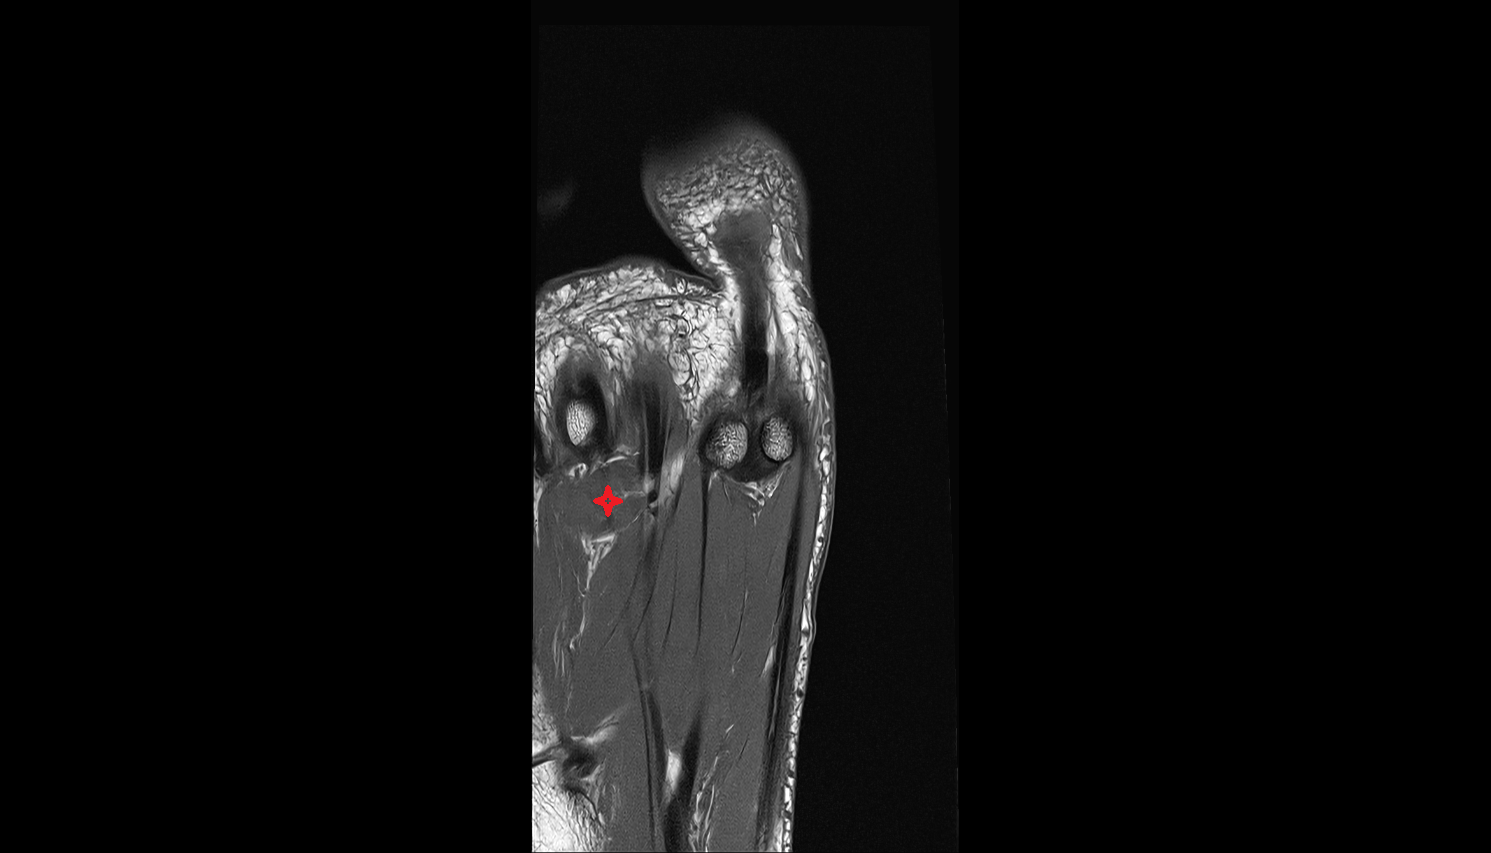

- Plantar aponeurosis